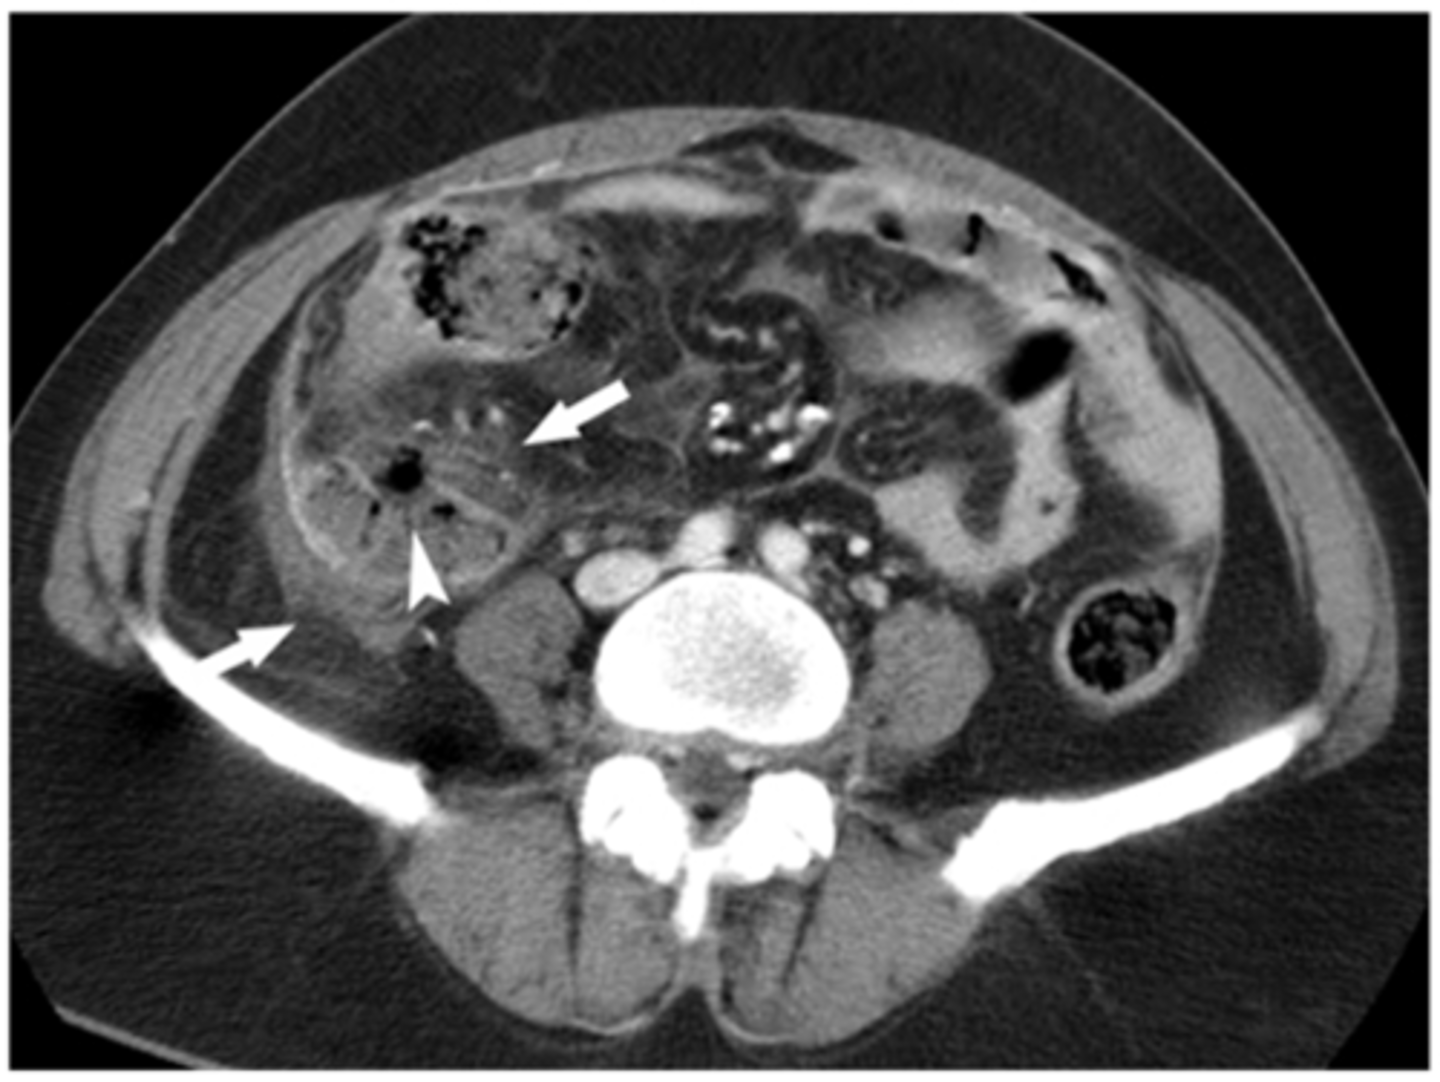

Incisional hernia

A type of hernia caused by an incompletely-healed surgical wound